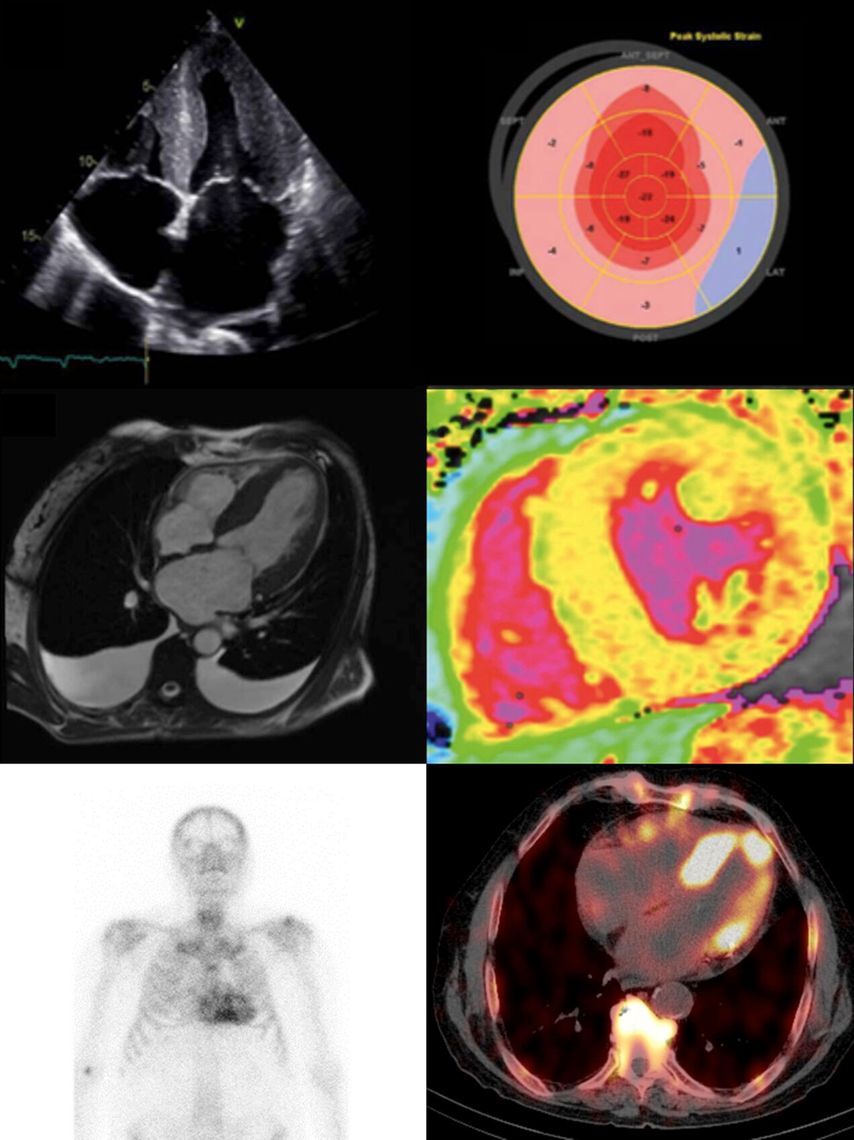

Während die ATTR-CM einst als seltene Erkrankung angesehen wurde, haben zunehmende Awareness sowie Fortschritte bei diagnostischen Methoden und Algorithmen in den letzten Jahren dazu beigetragen, dass heutzutage immer mehr Betroffene diagnostiziert werden.3 Dabei nehmen vor allem bildgebende Verfahren wie die Echokardiografie einen hohen Stellenwert ein, die anhand sogenannter „red flags“ wertvolle Hinweise auf das Vorliegen einer kardialen Amyloidose geben können. Diese umfassen eine biventrikuläre Verdickung, insbesondere im Bereich des Septums, dilatierte Vorhöfe mit hypertrophiertem interatrialem Septum, Perikard- und/oder Pleuraergüsse (Abb. 1a) sowie das charakteristische Muster einer basal reduzierten und apikal erhaltenen longitudinalen Funktion der linksventrikulären Wandabschnitte in der Strain-Analyse („apical sparing“, Abb. 1b).4 Darüber hinaus erlaubt die kardiale Magnetresonanztomografie (MRT), mittels kontrastmittelgestützter „Late-Enhancement“-Aufnahmen und T1-Mapping-Sequenzen myokardiale Amyloidablagerungen in der extrazellulären Matrix zu erfassen (Abb. 1c und 1d), wodurch eine zuverlässige differenzialdiagnostische Abgrenzung zu anderen hypertrophen Erkrankungsformen möglich ist.5

Abb. 1: Bildgebende Verfahren zur Diagnostik einer Transthyretin-Amyloid-Kardiomyopathie (ATTR-CM) (Quelle: eigene Anfertigung)

Eine diagnostische Schlüsselrolle wird jedoch nuklearmedizinischen Verfahren wie der planaren Ganzkörper-Knochenszintigrafie mit radioaktiv markierten Amyloid-affinen Tracern (wie z.B. 99mTc-DPD) zugeschrieben (Abb. 1e).6 Diese ermöglicht die Visualisierung myokardialer Amyloidablagerungen und hat sich als nichtinvasiver Goldstandard mit hoher Sensitivität und Spezifität für die Diagnose der ATTR-CM etabliert, indem die Amyloid-bedingte Tracer-Anreicherung semiquantitativ mittels des visuellen Perugini-Scores beurteilt wird.7 Hierbei gilt es jedoch anzumerken, dass die planare Bildgebung einigen Limitationen unterliegt. Dazu gehören zum einen falsch-positive Befunde aufgrund von „Radiotracer-Blutpooling“, die fälschlicherweise als Anreicherung im Myokard interpretiert werden, und zum anderen sind planare bildgebende Verfahren nicht in der Lage, den progredienten Krankheitsverlauf zu quantifizieren oder Amyloid-spezifische Therapien zu monitieren.8 Diese potenziellen Limitationen können durch quantitative Verfahren wie die SPECT/CT-Bildgebung (Single Photon Emission Computed Tomography/Computed Tomography) verringert werden (Abb. 1f).9 Anhand quantitativer Bildgebungsbiomarker, welche die Konzentrationen des radioaktiven Tracers im Gewebe widerspiegeln, kann eine umfassende Quantifizierung myokardialer Amyloidablagerungen erfolgen. Bei serieller Anwendung bietet dies zudem das Potenzial, den Krankheits- und Therapieverlauf zu überwachen.10,11